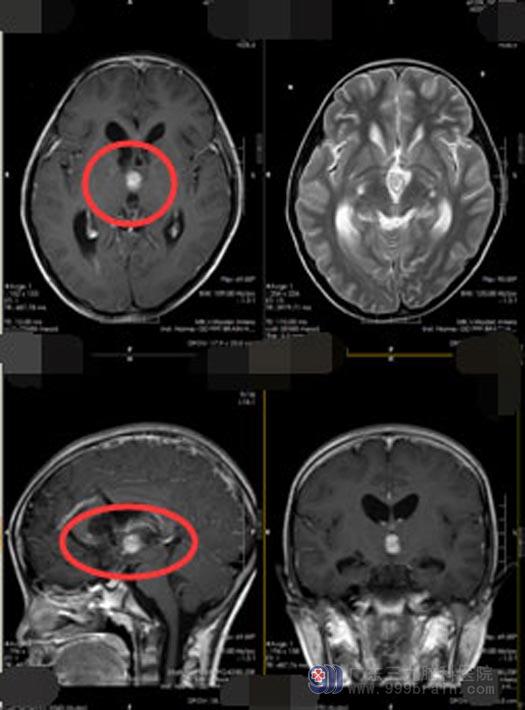

家人焦急万分,经过多方打听并最终坚定地选择了广东三九脑科医院神经外五科。入院时,小星留置双侧脑室外引流管,生命体征平稳,头颅MR示:脑室系统积血,双侧额叶-侧脑室引流管置入改变;此时需要面对的问题是:脑室引流管留置时间较长,需尽早完善术前准备并进行手术,避免出现颅内感染。

详尽的术前讨论并制定缜密的手术计划后,医院副院长、神经外五科主任鲁明带领手术团队为小星实施“三脑室-松果体区肿瘤病变切除术”,肿瘤在三脑室及松果体区,位于颅脑深部,肿瘤周围布满重要的颅神经及脑血管,风险非常高;如果在切除过程中损伤了正常脑神经或血管将会造成很严重的后果。所幸手术进行得非常顺利,完整地切除了肿瘤并很好的保护了正常的脑组织。

▲手术前